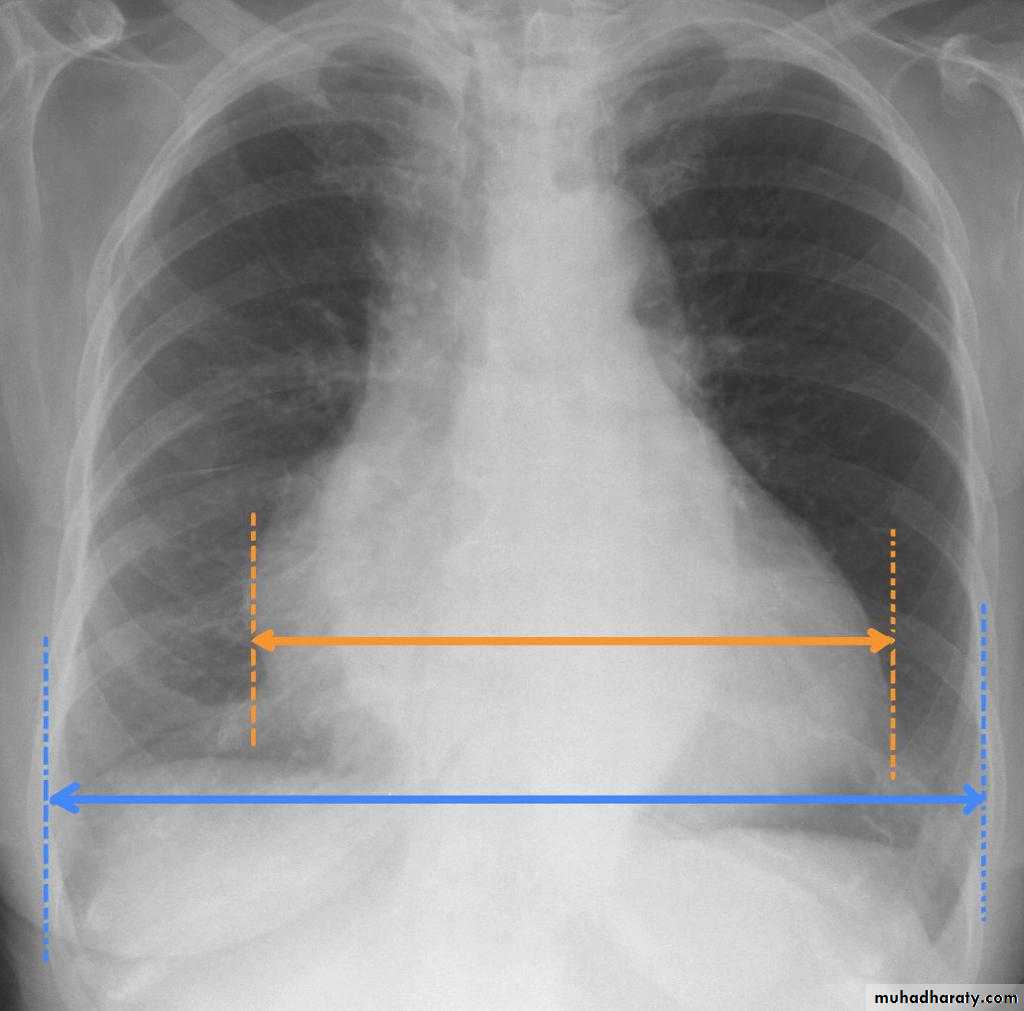

Who to asses cardiac size

Cardiac borders in AP view

13.who to asses cardiac size

14.cardiac border in AP view